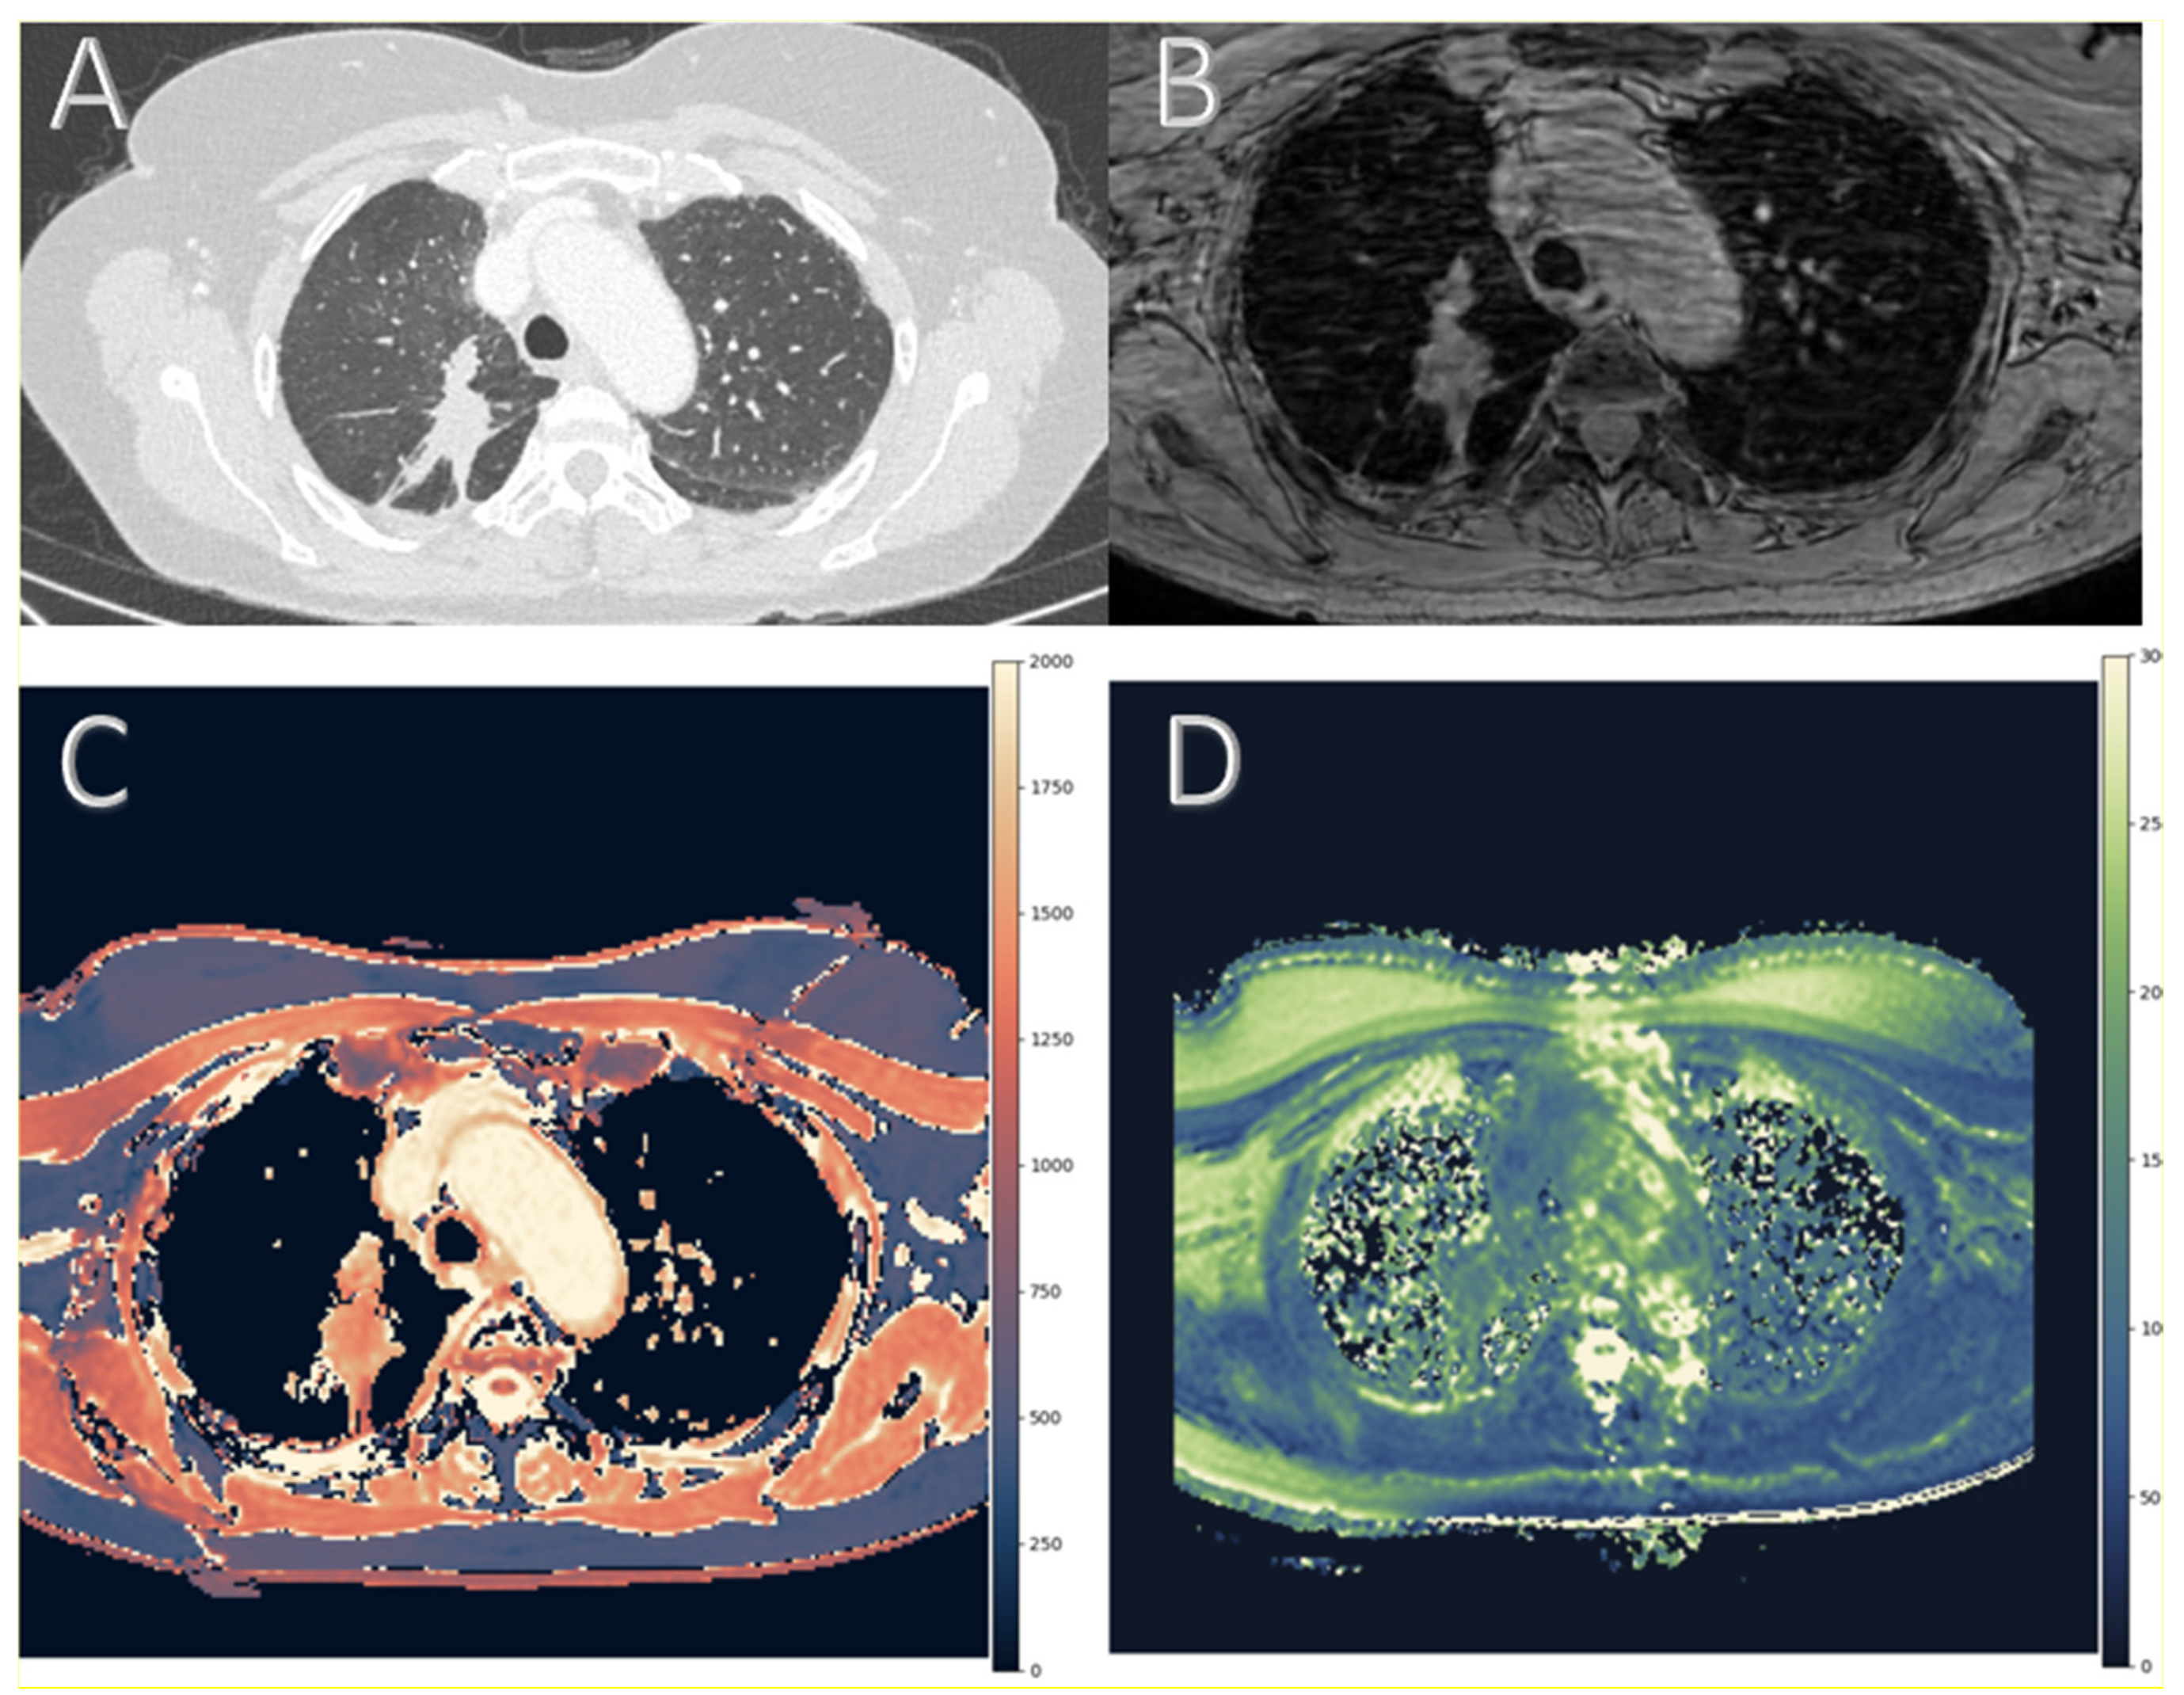

For image analysis, two radiologists with 7 and 9 years of experience in thoracic imaging independently placed regions of interest (ROIs) within each target lesion on both T1 and T2 maps. ROI placement was performed manually using a circular or elliptical shape adapted to the morphology of the lesion. To ensure reproducibility while accounting for lesion size and heterogeneity, each lesion was sampled with up to four ROIs positioned within the most solid and homogeneous areas, preferably on the slice showing the greatest axial extent of the lesion. This cap was pre-specified to balance spatial heterogeneity in sampling (core versus periphery) and reading time. ROI sizes typically ranged from 5 to 20 mm2, with adjustments made according to lesion size. For smaller lesions, the ROI was minimized to fit completely within the lesion boundaries to avoid partial volume effects. For larger lesions, multiple ROIs were placed to better represent spatial heterogeneity. ROIs were carefully drawn to exclude necrotic areas, cavitation, bronchi, calcifications, or adjacent vessels and lung parenchyma. Figure 1 illustrates the imaging workflow and generation of relaxometry maps by showing the multimodal imaging of a histologically confirmed primary lung cancer.

Figure 1. Multimodal imaging of a histologically confirmed primary lung cancer in the right upper lobe. Axial thin-slice chest computed tomography (CT) used for anatomical reference and lesion localization (A). Respiratory-gated, AI-accelerated 3D gradient echo image (B). T1 relaxation time map and (C) T2 relaxation time map (both in ms) (D). Panels C and D are color-coded according to International Society for Magnetic Resonance in Medicine (ISMRM) guidelines for magnetic resonance (MR) relaxometry maps, using perceptually optimized diverging color scales [19].